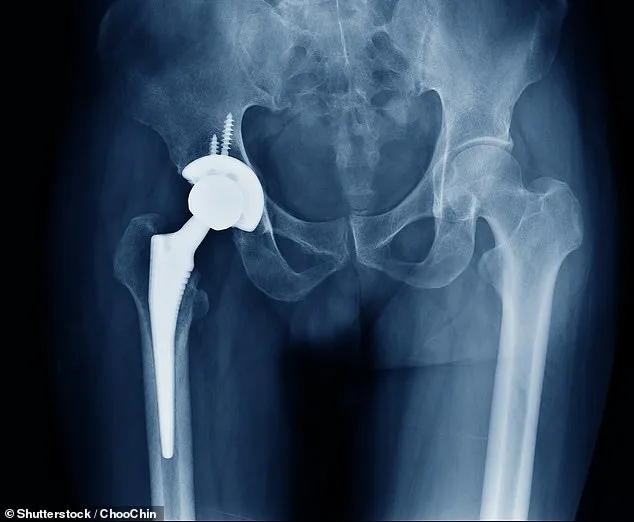

A crisis is unfolding in the UK's healthcare system as nearly a million patients face the prospect of having knee and hip replacement surgeries cancelled, according to the latest revelations from the NHS. The root of the problem lies in a 'critical machine failure' at Heraeus, the NHS's primary supplier of bone cement, a crucial component used in over 80% of knee replacements and 60% of hip replacements. With just one week of supply remaining, hospitals are scrambling to prioritize emergency cases, leaving thousands of patients in limbo.

The situation has escalated to a breaking point, with 850,000 individuals in England currently waiting for joint replacement surgery. Of these, 200,000 procedures in 2024 alone required bone cement, a material now in global short supply. Hospitals have been instructed to cancel surgeries scheduled for the next two months, a decision that will disproportionately affect those who have waited over a year for treatment. Experts warn that this could lead to wait times reminiscent of the pandemic era, when backlogs stretched for months and patients faced unprecedented delays.